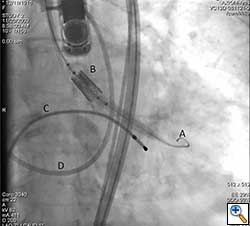

The Sapien valve is a balloon expandable platform and it comes in two sizes, 23 mm and 26 mm. The valve is prepared and mounted onto a sheath system for implantation on the back table. The femoral arterial access is serially dilated to accommodate a 22 French (for 23 mm Sapien valve) or a 24 French (for 26 mm Sapien valve) sheath. The balloon mounted valve is then advanced in a retrograde fashion into the aortic valve position using angiographic and echocardiographic guidance (Figure 2). It is important to visualize the position of the valve using at least 2 different angles. For the transfemoral approach, the recommended positioning of the prosthesis is 60%-40%, which is 60% of the prosthesis should be on the ventricular side of the aortic annulus with 40% of the prosthesis on the aortic side of annulus. This is due to the past experience observation that the prosthesis has a tendency to migrate in the aortic direction during deployment. This phenomenon is likely a result of the stored torque in the delivery system when introduced from the femoral artery. For ease of prosthesis arch transit, the delivery platform is equipped with the Retroflex system from Edwards. Of note, the correct orientation of the prosthesis should be confirmed both visually prior to placement into the introducer sheath and angiographically prior to deployment. Next, transvalvular flow is severely depressed by rapid ventricular pacing. The valve is then balloon expanded rapidly and implanted in position. If there is moderate to severe aortic insufficiency from a paravalvular leak after the deployment, a second ballooning with a larger volume is performed under conditions of rapid ventricular pacing.